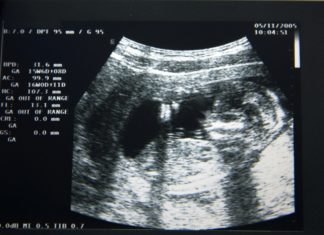

Hilarische echo: ‘Ik dacht dat ik zwanger was van een vogel’

Het moet één van de mooiste momenten van de zwangerschap zijn: de echo waarop je voor het eerst jouw baby kunt bekijken. Dit moment werd zeker speciaal...